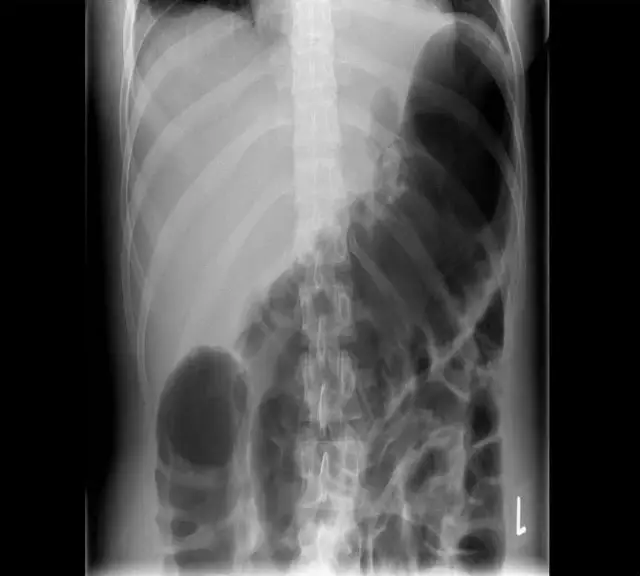

一位40歲女士罹患潰瘍性大腸炎( ulcerative colitis)數年,昨天起出現嚴重腹痛及腹瀉的症狀,且合併發燒。至醫院急診就醫時發現有白血球增多的現象 (leukocytosis),腹部X光片顯示如圖。請問其最可能的診斷為下列何者? 圖片描述

提供的腹部 X 光片 (KUB) 顯示以下特徵:

1. 顯著的腸氣擴張:橫結腸 (transverse colon) 與降結腸段呈現極度擴張。從影像中與脊椎骨寬度相比,該腸段直徑明顯大於 6 公分 (中毒性巨結腸症的診斷標準之一)。

2. 結腸袋消失 (Loss of haustral markings):擴張的腸段邊緣平滑,缺乏正常的結腸袋 (haustra) 結構,這是由於嚴重的透壁性發炎 (transmural inflammation) 導致腸壁肌肉張力喪失及黏膜水腫所致。

3. 缺乏特定的扭轉徵象:影像中並未見到乙狀結腸扭轉典型的「咖啡豆徵象 (Coffee bean sign)」,顯示為整段或廣泛性的結腸擴張而非單一腸氣環的扭轉。

患者有潰瘍性大腸炎病史,急性發作並出現發燒、腹痛、白血球過高 (Leukocytosis)。腹部 X 光顯示橫結腸顯著擴張 (>6cm) 且失去結腸袋紋路。這些發現完全符合 中毒性巨結腸症 (Toxic Megacolon) 的臨床與放射學診斷標準。因此最可能的診斷為 (C)